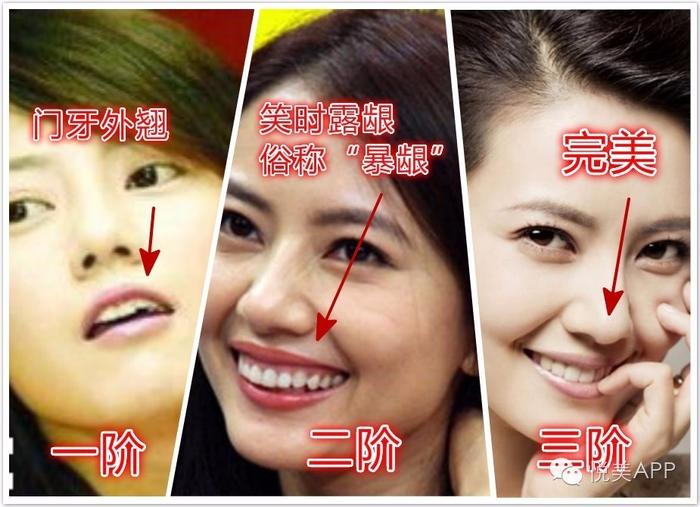

高圆圆早期的苦情脸出名极了,比小白菜还苦~整张脸都在扑刷刷往下掉,最关键是原生牙门牙外翘,强行闭口才可以将牙齿完全遮盖住,导致整个嘴——凸,嘴角更加下垂~

蓝后就开始了漫漫整牙路~,先解决牙列不齐的问题,通过戴牙套把牙齿排排齐,然后再解决“露龈笑”的问题~

这些硬伤都解决掉以后,现在你看到女神高圆圆,才敢各种开怀大笑啊~